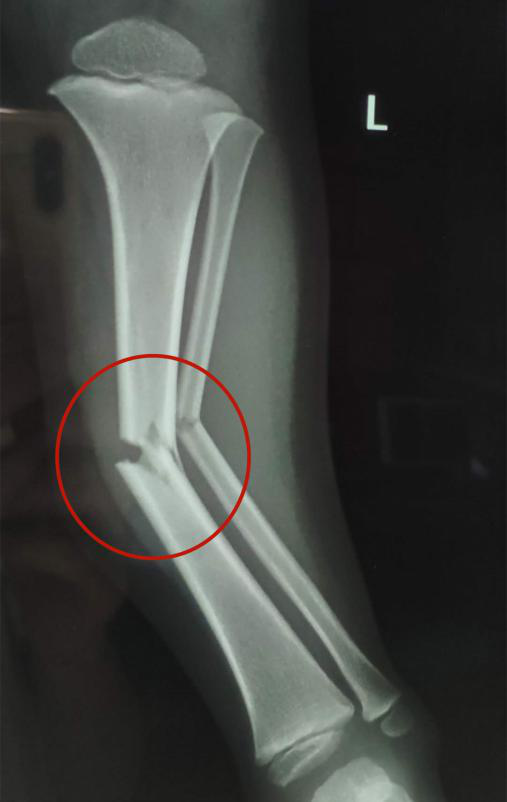

接診的瀘州市中醫(yī)醫(yī)院骨傷一科副主任中醫(yī)師李孟澤查看了患兒之前的X光片及左下肢情況,發(fā)現(xiàn)其骨折移位較大(骨折處彎曲呈30度角以上),導致左下肢中段嚴重畸形。

復位后,經(jīng)再次照X光顯示,患兒左下肢脛腓骨斷端緊密對合,外觀畸形得以糾正,手法復位治療非常成功。

手法復位前X片顯示脛腓骨斷端,左下肢中段嚴重畸形